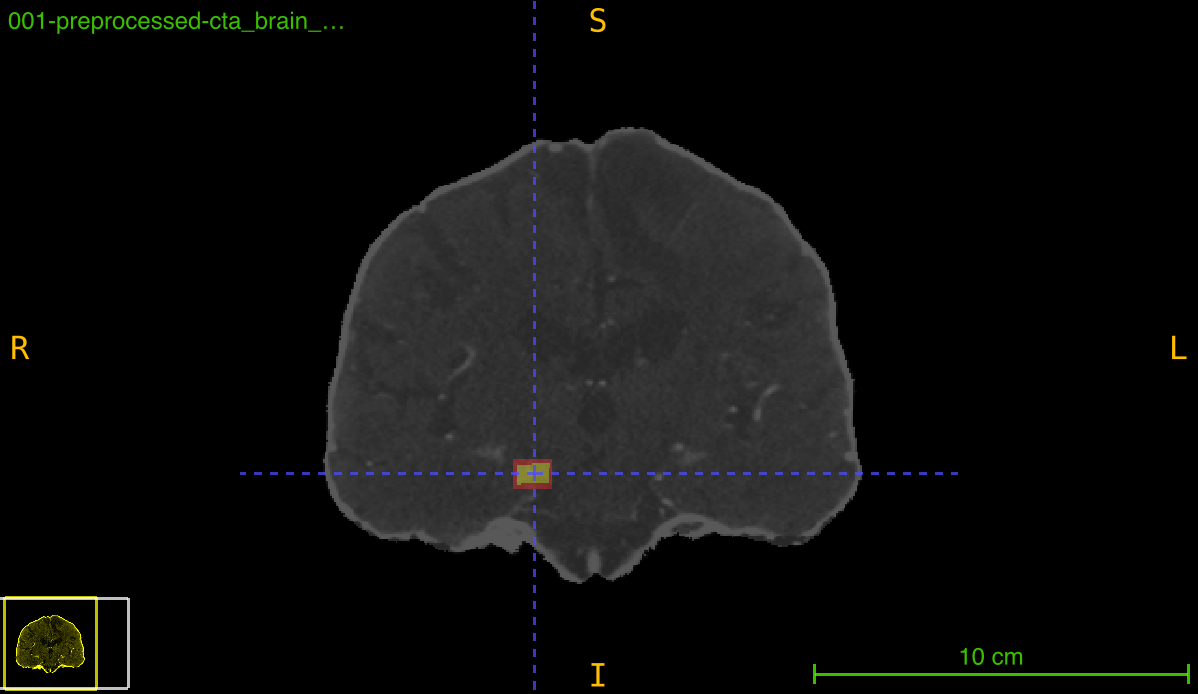

Visualize Transformed Annotations

Create visual comparison of annotations:

from nidataset.preprocessing import register_annotation

import nibabel as nib

import matplotlib.pyplot as plt

import numpy as np

# Register with recalculation

register_annotation(

annotation_path="lesion_bbox.nii.gz",

transform_path="transforms/transformation.tfm",

registered_path="registered/scan_registered.nii.gz",

output_path="registered/bbox_recalc.nii.gz",

recalculate_bbox=True

)

# Register without recalculation

output_path="registered/bbox_deformed.nii.gz",

recalculate_bbox=False

# Load for visualization

scan = nib.load("registered/scan_registered.nii.gz").get_fdata()

bbox_recalc = nib.load("registered/bbox_recalc.nii.gz").get_fdata()

bbox_deformed = nib.load("registered/bbox_deformed.nii.gz").get_fdata()

# Select middle slice

mid_slice = scan.shape[2] // 2

# Create visualization

fig, axes = plt.subplots(1, 3, figsize=(18, 6))

# Original scan

axes[0].imshow(scan[:, :, mid_slice], cmap='gray')

axes[0].set_title('Registered Scan', fontsize=14)

axes[0].axis('off')

# With recalculated bbox

axes[1].imshow(scan[:, :, mid_slice], cmap='gray')

axes[1].imshow(bbox_recalc[:, :, mid_slice], cmap='Reds', alpha=0.4)

axes[1].set_title('Recalculated BBox\n(Axis-aligned)', fontsize=14)

axes[1].axis('off')

# With deformed bbox

axes[2].imshow(scan[:, :, mid_slice], cmap='gray')

axes[2].imshow(bbox_deformed[:, :, mid_slice], cmap='Blues', alpha=0.4)

axes[2].set_title('Deformed BBox\n(Preserves shape)', fontsize=14)

axes[2].axis('off')

plt.tight_layout()

plt.savefig('annotation_comparison.png', dpi=150, bbox_inches='tight')

print("Visualization saved: annotation_comparison.png")